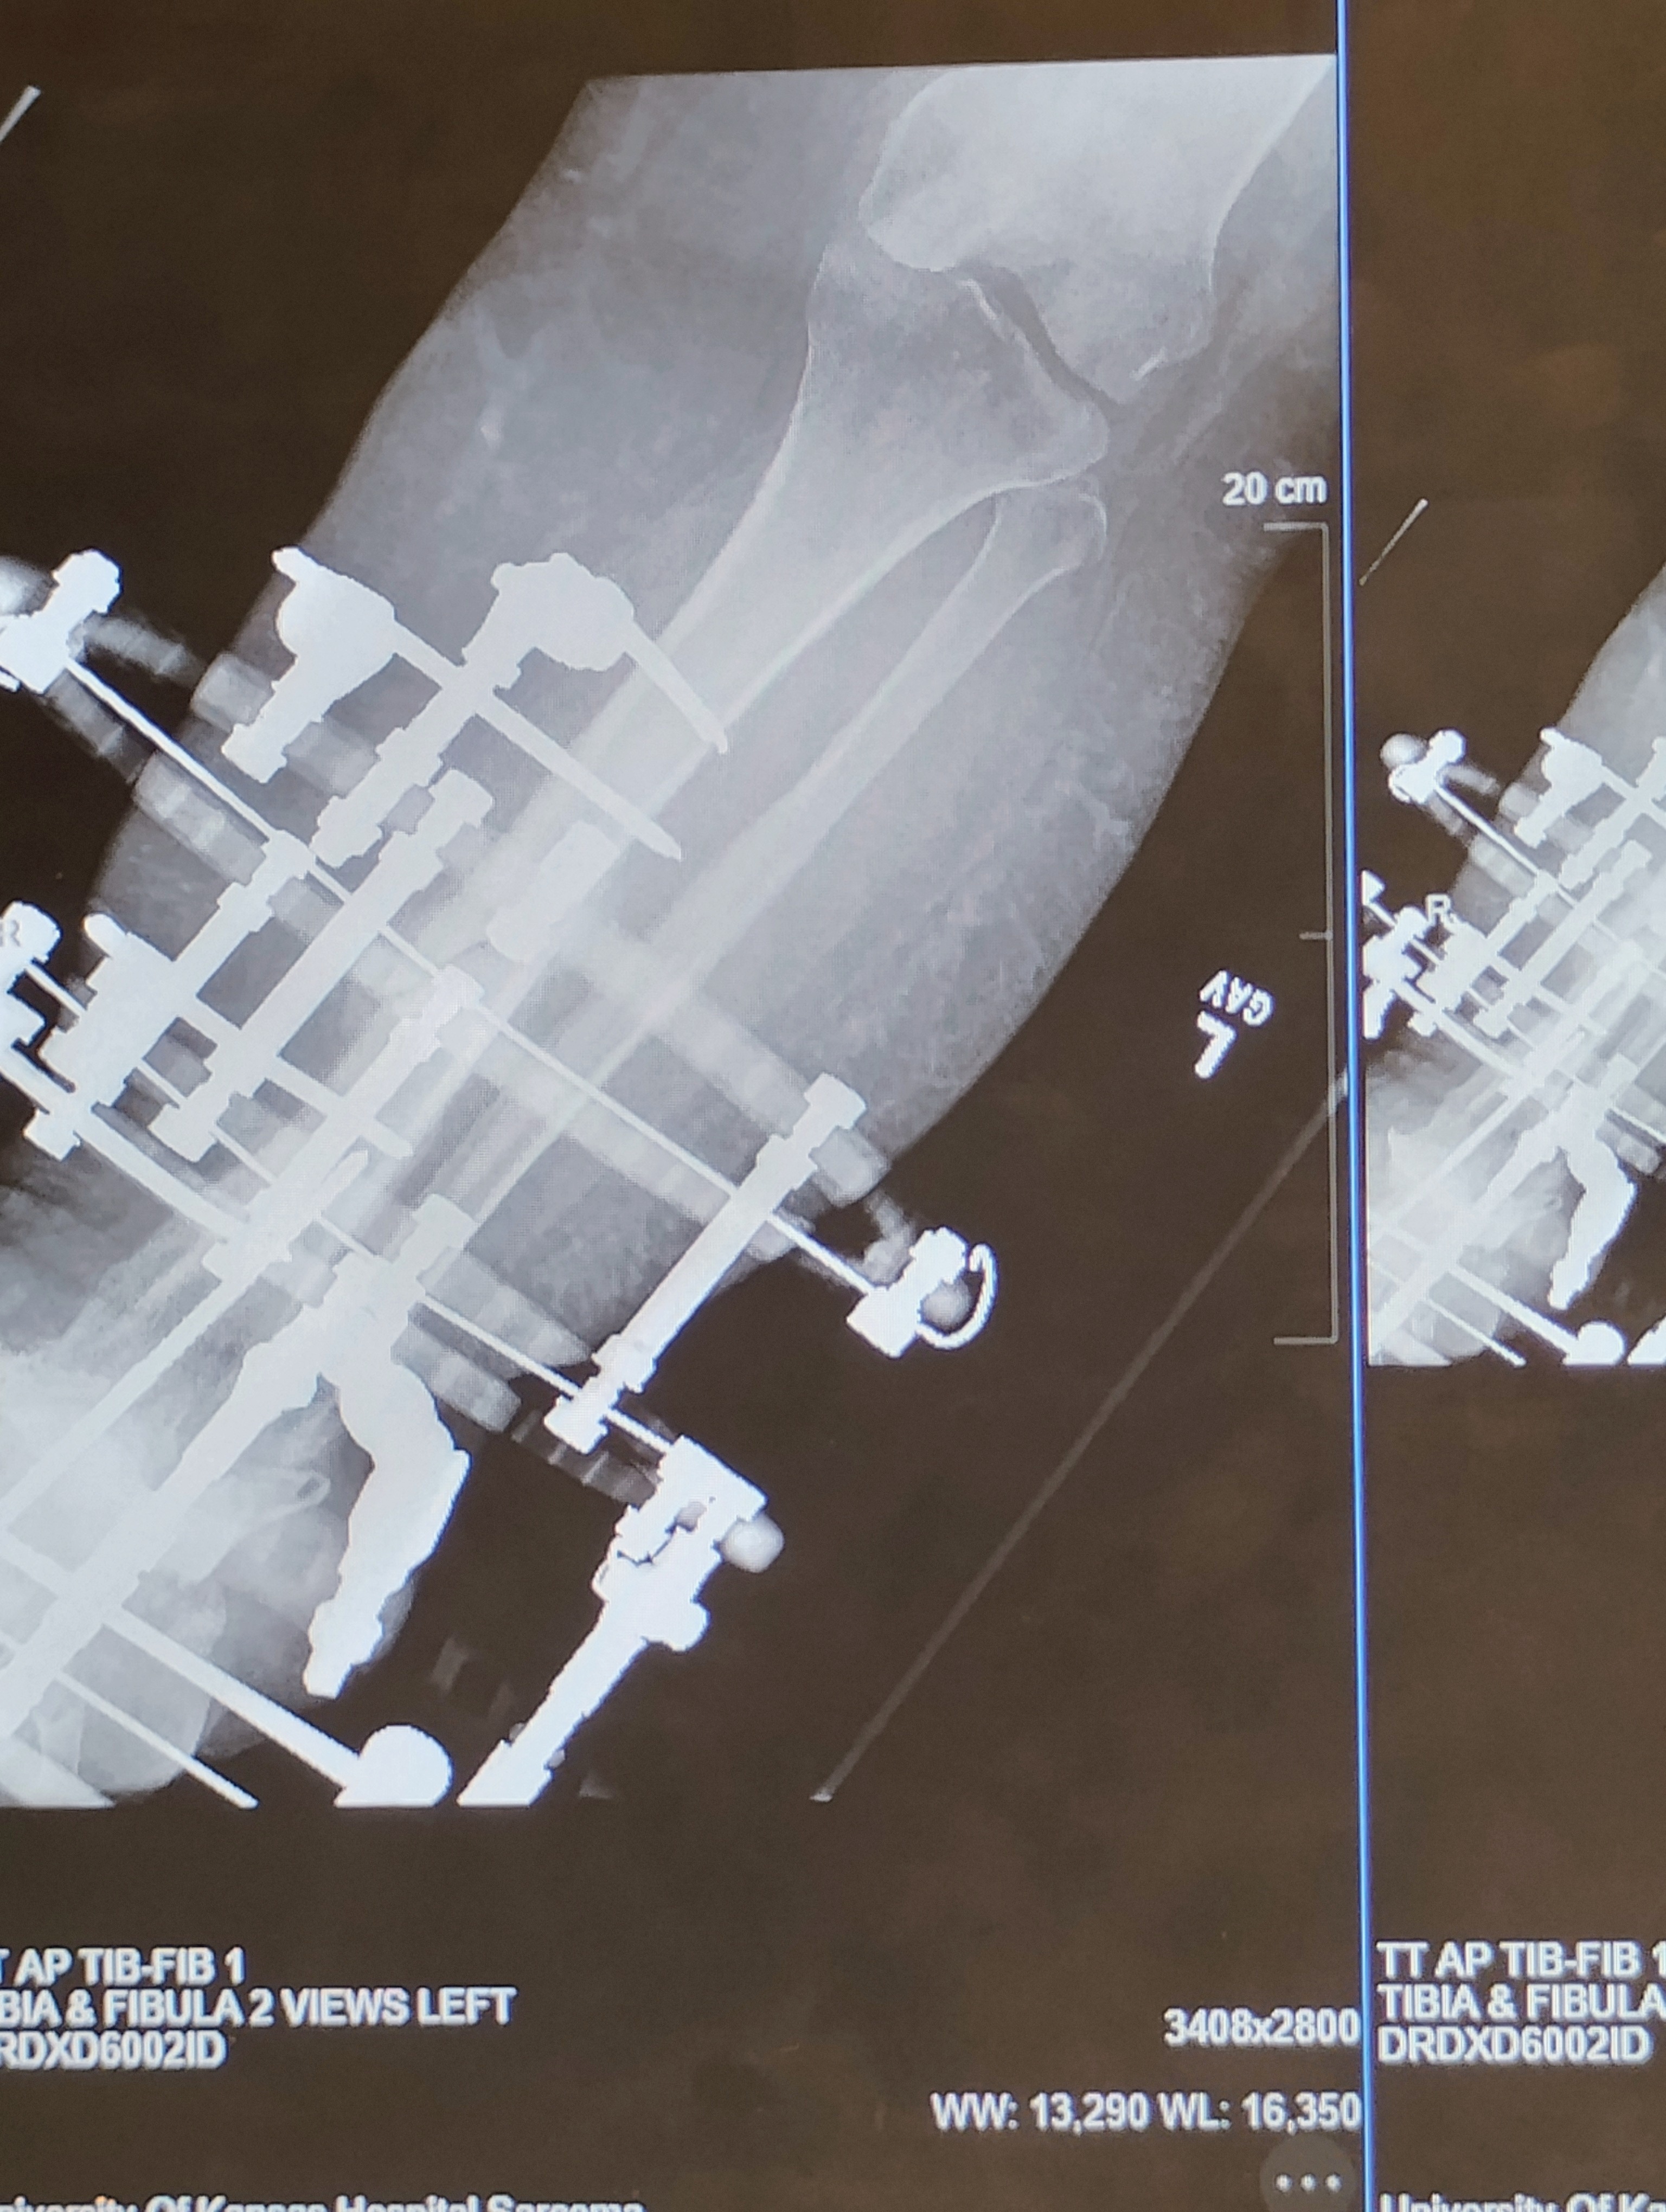

Hi, my name is Cristina. I am a disabled single momma of 3. This year has been full of challenges. I became wheelchair-bound 100% a little over a year ago. I developed something called Charcot foot, which deteriorated the bones in my foot and left me fighting amputation. I finally found a doctor who would help me, so I ended up with an external fixator on for almost 3 months. I finally got it off, and I'm now wearing a cast.